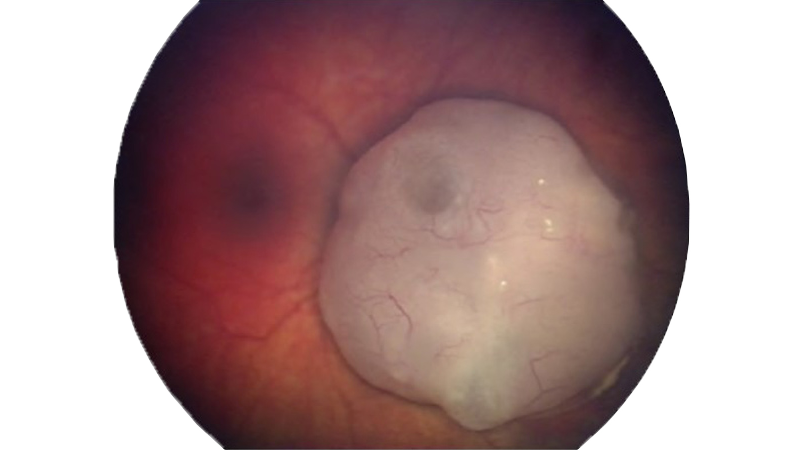

1. Retinoblastom

Das Retinoblastom (Bild 2) ist eine Art von Augenkrebs, bei dem sich Krebszellen in der Netzhaut eines Auges oder beider Augen bilden (Bild 2). Das Retinoblastom betrifft am häufigsten Säuglinge und Kleinkinder, tritt jedoch nur selten bei Kindern im Alter über sechs Jahren auf.

Das durchschnittliche Alter von Kindern, die mit einem Retinoblastom diagnostiziert werden, beträgt zwei Jahre. Jedoch werden manche Kinder möglicherweise bereits mit Tumoren geboren. Das Retinoblastom ist eine seltene Krebserkrankung, die etwa 2 % der Krebserkrankungen im Kindesalter ausmacht. Nach Angaben der American Cancer Society werden in den USA jedes Jahr ca. 200 bis 300 Kinder mit Retinoblastom diagnostiziert3.

Das Retinoblastom wird durch DNA-Veränderungen (genetische Mutationen) der Nervenzellen in der Netzhaut verursacht. Diese Mutationen führen dazu, dass die Zellen weiter wachsen und sich vermehren, wenn gesunde Zellen absterben würden. Diese sich sammelnde Masse von Zellen bildet einen Tumor.

Jede Zelle verfügt normalerweise über zwei RB1-Tumorsuppressoren, die steuern, wie schnell die Zellen wachsen, und Zellen zur richtigen Zeit absterben lassen. Mit wenigstens einem funktionsfähigen RB1-Gen bildet die Netzhautzelle kein Retinoblastom. Wenn jedoch beide RB1-Gene eine Mutation aufweisen, kann die Zelle unkontrolliert wachsen. Dies verursacht weitere Genveränderungen, die möglicherweise dazu führen, dass Zellen zu Krebszellen werden. Die RB1-Mutation kann entweder in allen Zellen des Körpers oder in nur einer Zelle in einem einzigen Auge auftreten:4

Symptome des Retinoblastoms

Das Retinoblastom wird häufig erkannt, weil das Auge eines Kindes ein ungewöhnliches Erscheinungsbild aufweist. Wenn Licht in das Auge eintritt, reflektiert die Netzhaut gewöhnlich einen kleinen Teil des Lichts durch die Pupille zurück. Aufgrund der Blutgefäße im hinteren Augenabschnitt weist das reflektierte Licht eine rötliche Farbe auf, die als Fundusrotreflex bezeichnet wird. Abnormalitäten in der Netzhaut können entweder einen fehlenden Fundusrotreflex verursachen oder auch einen weißen Pupillarreflex, der als Leukokorie bezeichnet wird.7